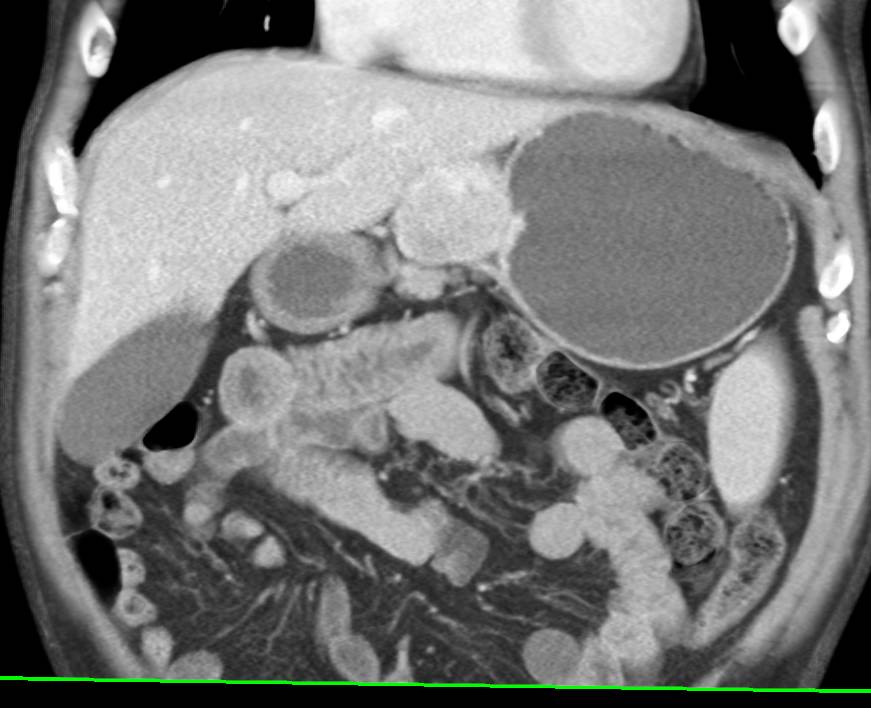

Vascular Repair with Multiple Stents